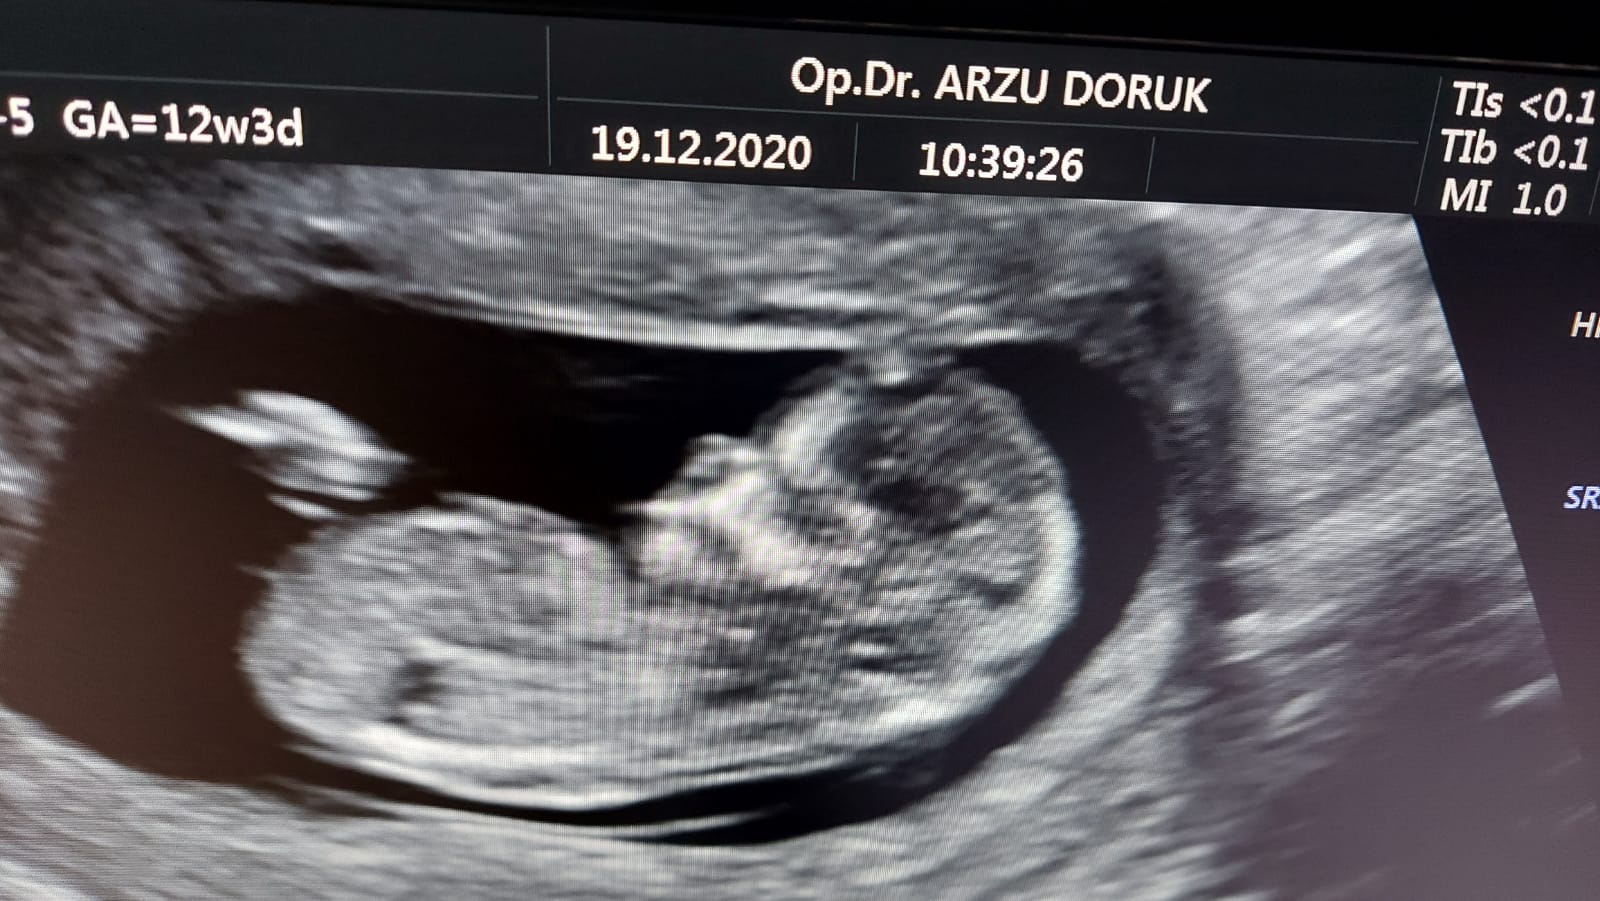

Merhaba, bizim cinsiyet hala kesinleşmedi 🙂 ben biraz nubu araştırdım. Ve size ilk gönderdiğim resimde nub kısmının dik olduğunu gördüm. Ama aynı anda verilen diğer görüntü aşağıda fakat burda da nubu paralel gözüküyor. Kafam karıştı açıkcası. Hangisi sizce?

Ekli dosyalar

• IMG-20210215-WA0022.jpg

IMG-20210215-WA0022.jpg

139,6 KB · Görüntüleme: 432

Emin olmamakla birlikte kız gibi görünüyor canım umarım sağlıklı kucağına alırsın sonucu kesin öğrendiğinde de yazarsan sevinirim :hamis: :d040: